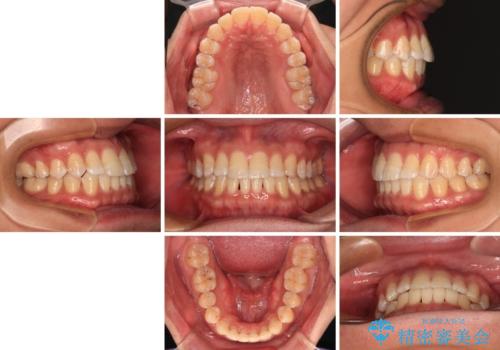

【モニター】楽して治したい メタルブラケットによる矯正治療

- メタルブラケット

- 1年4ヶ月

- 前歯のデコボコを気にして来院された患者様です。

インビザラインによるマウスピース矯正も適用となる歯列でしたが、できる限り自己管理の煩わしさのない状態で治したいとのことで、ワイヤー装置にて矯正治療を行うこととしました。

予定していた期間より長くかかりましたが、1年強できれいな歯列に仕上がりました。